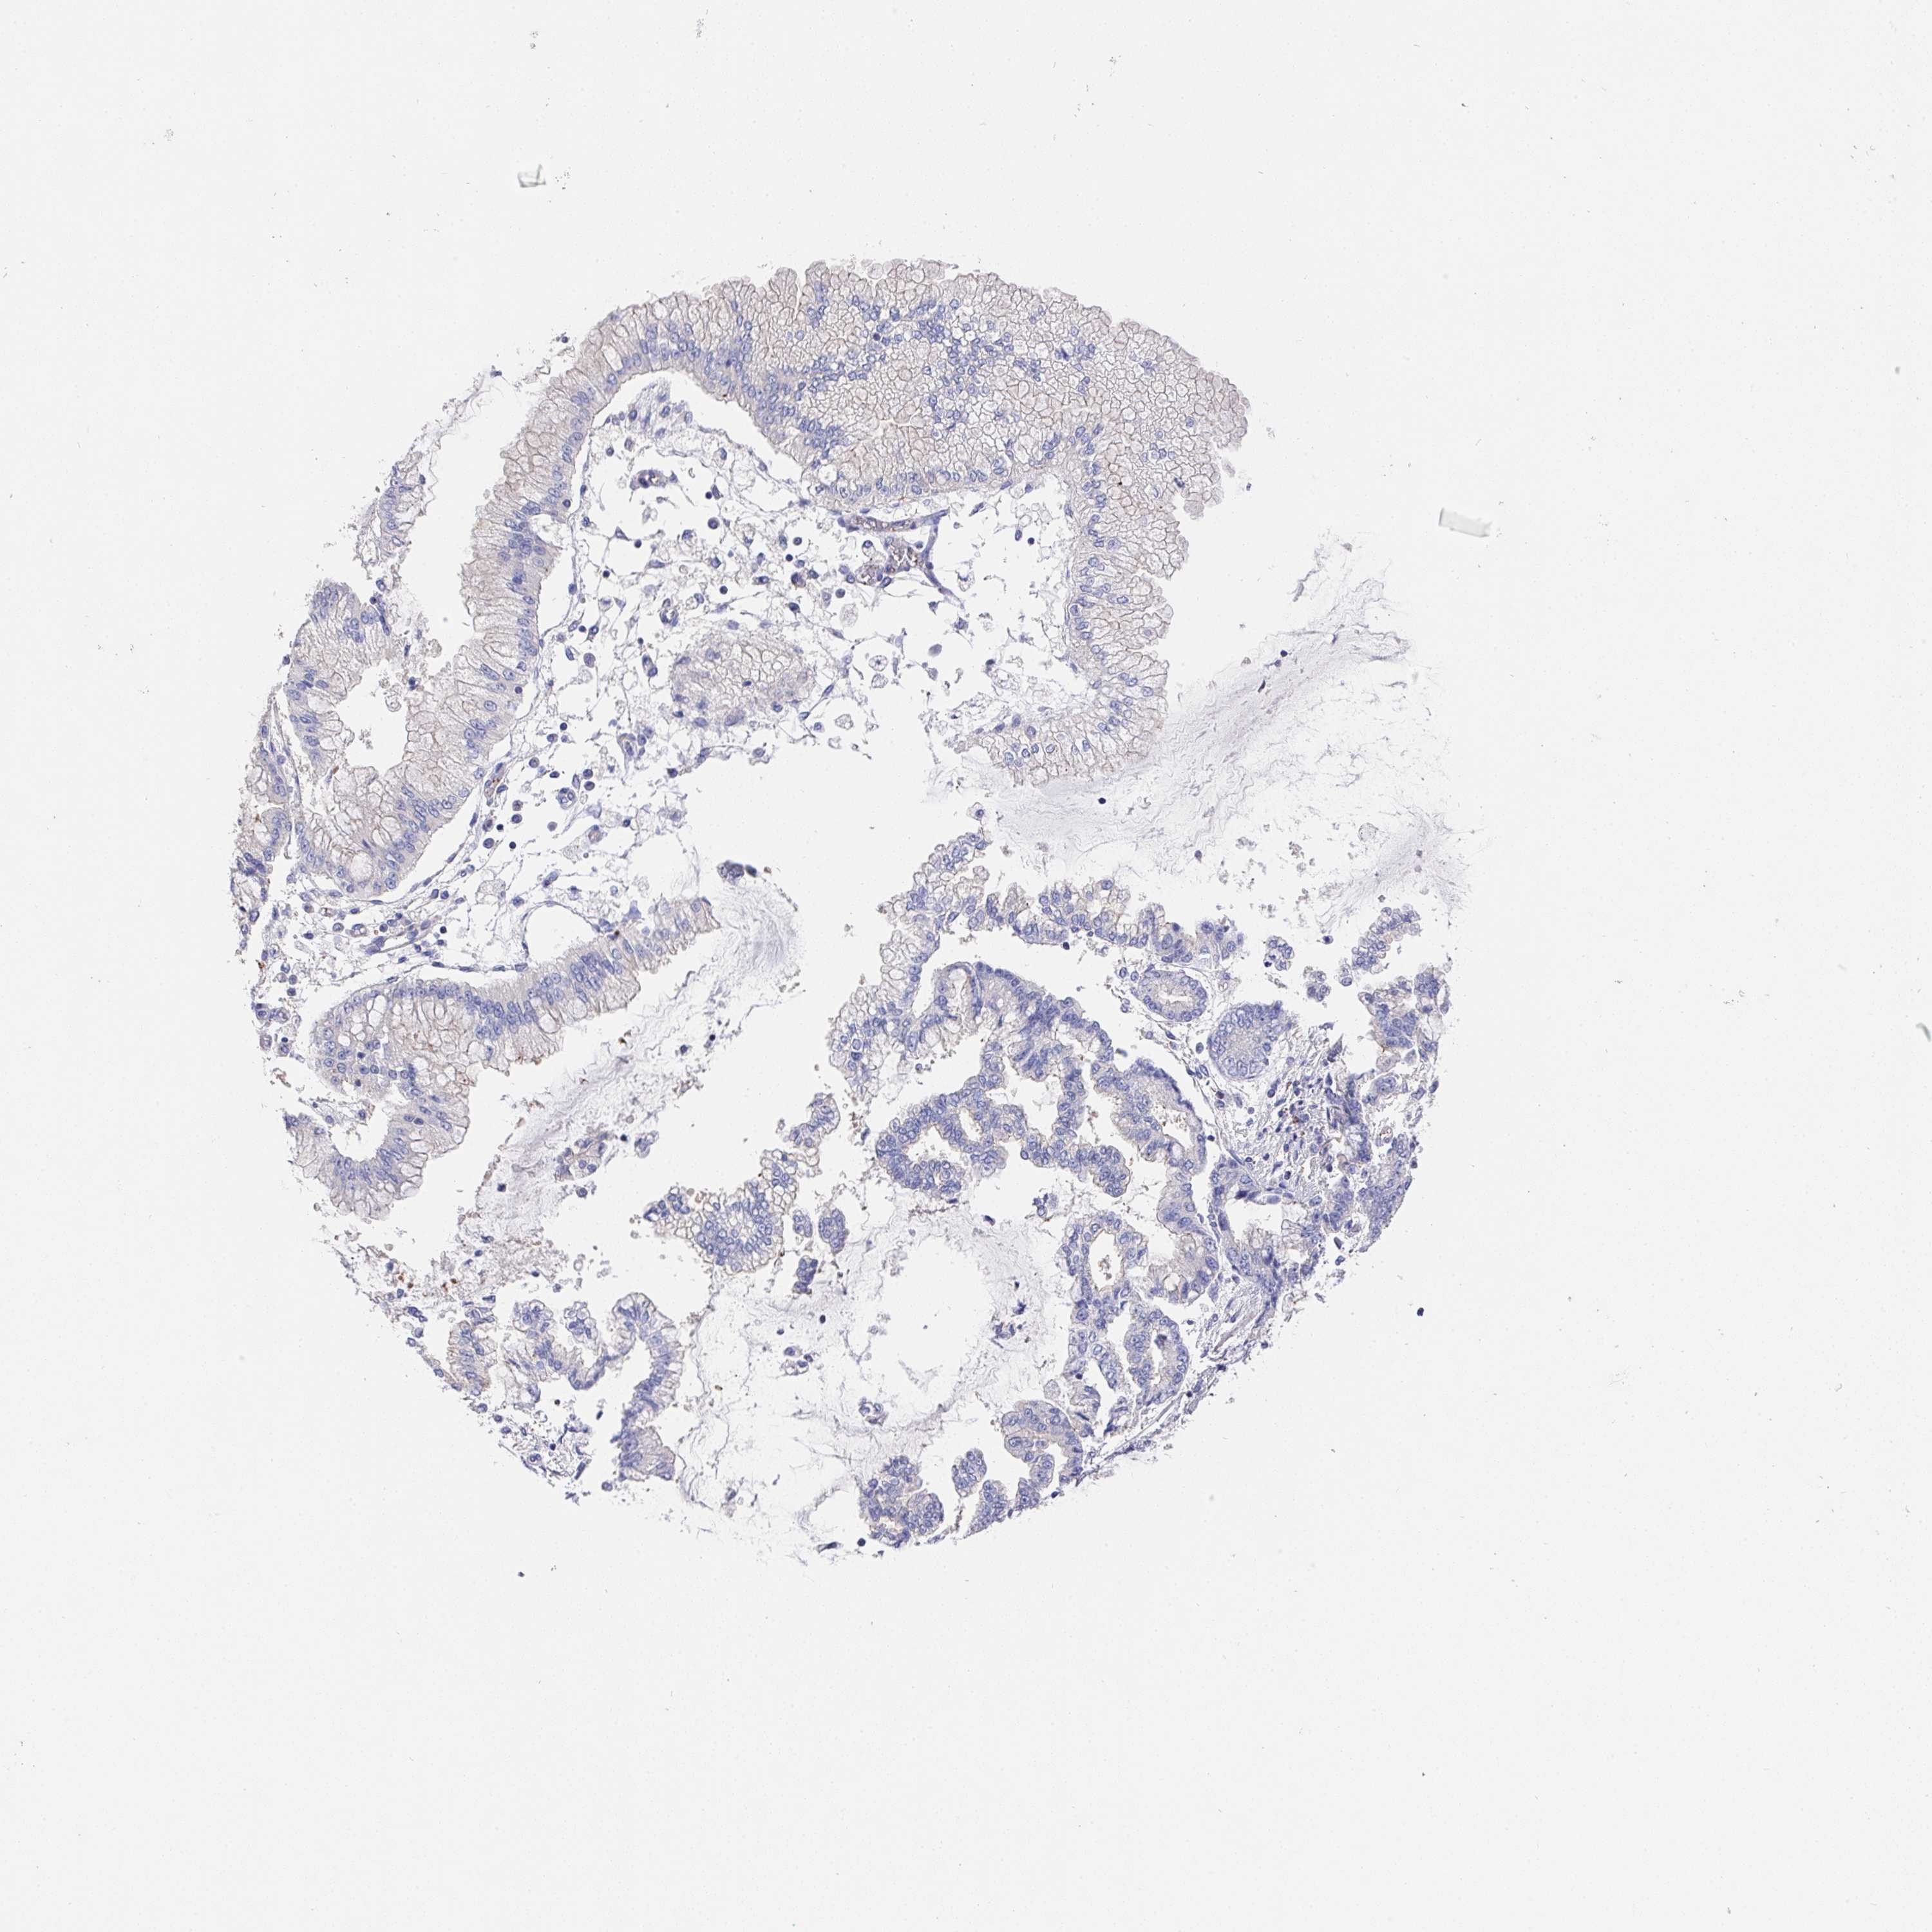

STOMACH CANCER - Protein expressioni

A mouse-over function shows sample information and annotation data. Click on an image to view it in a full screen mode. Samples can be filtered based on level of antibody staining by selecting one or several of the following categories: high, medium, low and not detected. The assay and annotation is described here.

Note that samples used for immunohistochemistry by the Human Protein Atlas do not correspond to samples in the TCGA dataset.

Antibody stainingi

Antibody staining in the annotated cell types in the current human tissue is reported as not detected, low, medium, or high, based on conventional immunohistochemistry profiling in selected tissues. This score is based on the combination of the staining intensity and fraction of stained cells.

Each image is clickable and will lead to virtual microscopy that enables deeper exploration of all samples and also displays staining intensity scores, fraction scores and subcellular localization as well as patient and tissue information for each sample.

Antibody HPA064183

Staining

High

Medium

Low

Not detected

Intensity

Strong

Moderate

Weak

Negative

Quantity

>75%

75%-25%

<25%

None

Location

Nuclear

Cytoplasmic/membranous

Cytoplasmic/membranous,nuclear

Adenocarcinoma, NOS